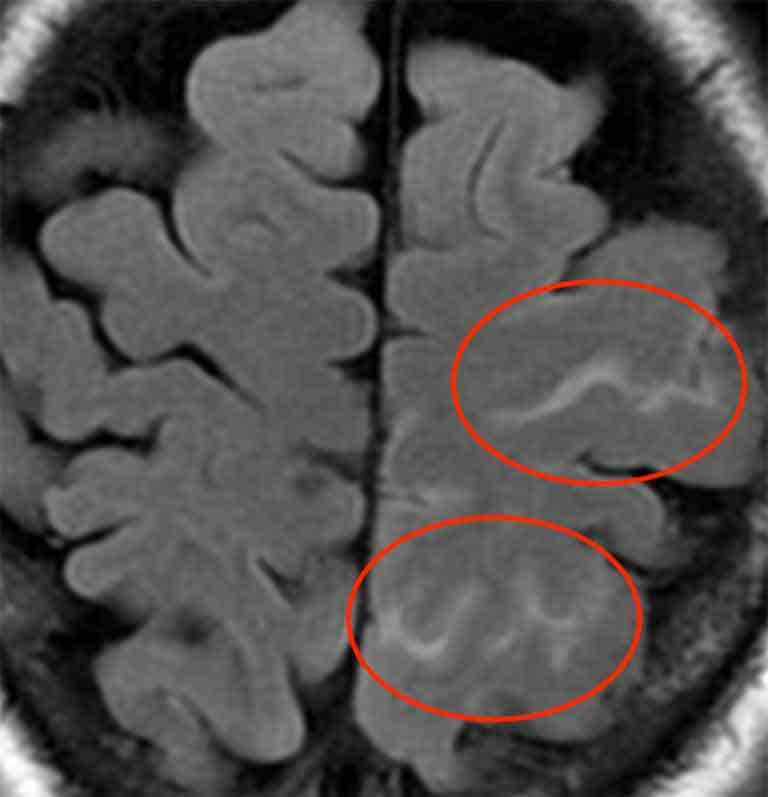

さらに、MRI検査でも異常を認めました。

前頭部から頭頂部にかけて、脳表面にくも膜下出血を生じていました。

可逆性脳血管攣縮症候群では、血管壁の破綻によりくも膜下出血を伴う事があります。